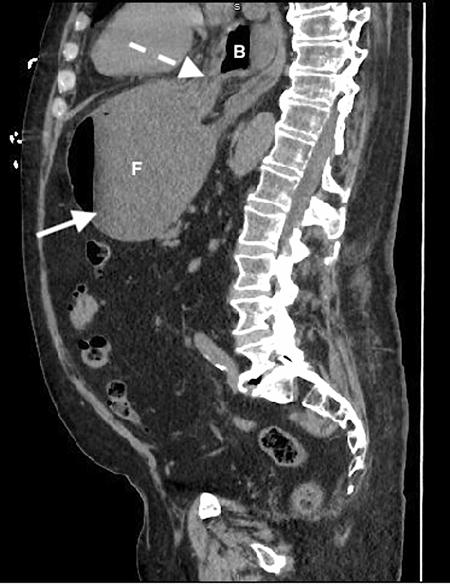

加急CT检查显示中至大型食管裂孔疝和由于胃扭转而呈现的胃部水肿膨胀并伴有部分梗阻(图3-5)。

(图5)

当怀疑有胃扭转时,选择初始的影像学检查非常重要,因为诊断延迟可能导致致命的并发症。CT检查高度可靠,主要有两种表现,即正常的胃窦幽门移行区和胃窦位置异常,诊断急性胃扭转的敏感性和特异性均为100%。POCUS是一种有效的非侵入性影像检查方式,主要用于床旁评估。此外,POCUS无辐射,并可根据临床情况随时进行重复检查。本例患者POCUS检查显示,胃部严重扩张,胃内容物分层,类似胃出口梗阻(GOO)的“黑白饼干”征象。POCUS还可以用来动态观察胃减压成功与否。